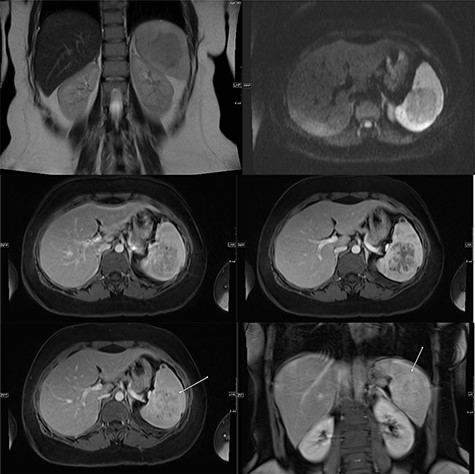

Abdominal ultrasonography showed a 5.0 × 5.0 cm well-defined, rounded, lobulated and hypoechoic vascular solid splenic lesion with no increased transmission or calcification. This lesion had vessels radiating from the center to the periphery (Fig. 1). Further evaluation with contrast-enhanced computed tomography (CT) of the abdomen showed a 6.0 × 5.6 × 4.4 cm solitary, rounded and lobulated non-calcified mass in the spleen, demonstrating heterogeneous, linear and nodular arterial enhancement with progressive filling in the portal venous and delayed phases (Fig. 2).

Ultrasound images with Doppler showing a well-defined rounded hypoechoic mass with vascularity in the peripheral areas as well as inside the lesion with no through transmission.